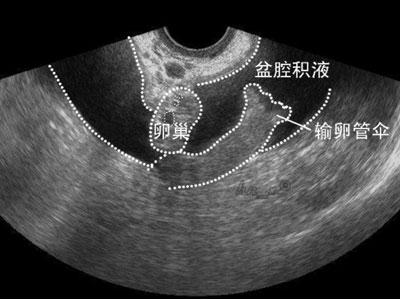

上面这张图片其实有点危言耸听了,盆腔积液也有非病理性的。

比如排卵的时候,卵泡液流入盆腔,那么B超看来就是盆腔积液,而这是非病理性的。

异位妊娠:就是通俗来说的“宫外孕”,如果说输卵管妊娠流产、破裂,都可以导致血液集聚在盆腔。此时一般还有停经、腹痛、不规则阴道流血。